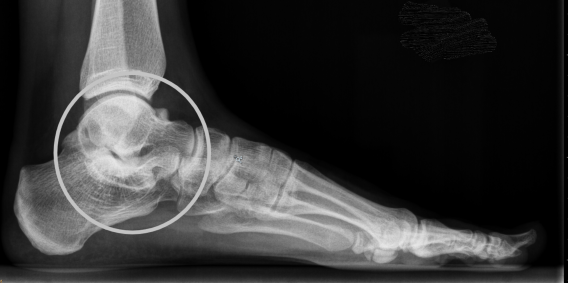

Een van de oorzaken van de stugge platvoet is de ‘tarsale coalitie’. Dit betekent dat de botten van de achtervoet niet goed zijn ontwikkeld, ze zitten niet los van elkaar zodat er een gewricht ontstaat, maar zijn aan elkaar vast gegroeid. Deze tarsale coalitie ontstaat al vroeg in de ontwikkeling en is waarschijnlijk al bij de geboorte aanwezig. Uit studies blijkt dat er mogelijk een erfelijke component is. Bij een tarsale coalitie ontwikkelen de gewrichten van de achtervoet zich niet goed. Er ontstaat een verbinding tussen de botten in plaats van een mooi gewricht. Over het algemeen ontstaat de verbinding tussen het hielbeen en het sprongbeen, de talocalcaneaire coalitie, of tussen het hielbeen en het scheepvormige botje, de calcaneonaviculare coalitie. Het kan ook op andere plekken voorkomen, maar dat is erg zeldzaam. Deze coalities kun je op een gewone röntgenfoto zien bij een kind vanaf een jaar of negen (dit is afhankelijk van de ontwikkeling van de groei van het kind). Als het op een gewone röntgenfoto niet goed te zien is, maar er wel een vermoeden is van een coalitie, wordt een CT-scan of een MRI-scan gemaakt.

De vergroeiing tussen het hielbeen en het scheepvormige botje, de calcaneonaviculare coalitie, bestaat vermoedelijk al bij de geboorte van het kind. De botten van een kind verbenen in de loop der jaren en elk botje heeft een andere tijd nodig om te verbenen. Hierdoor zijn in de eerste levensjaren de botten van kinderen veel flexibeler. Voor de achtervoet geldt dat deze vaak volledig ‘verbeend’ is tussen het 8ste en 14de levensjaar, wat dan ook betekent dat de klachten pas dan optreden. Door de verbening is de kanteling van de achtervoet niet goed mogelijk en kan een kind klachten krijgen van zwikken, pijn en stijfheid. Lang niet alle kinderen krijgen klachten van de coalitie!